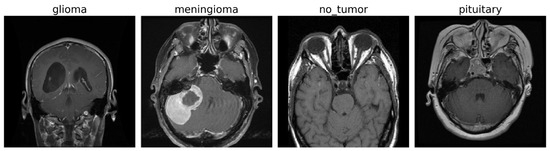

The experiments were conducted on a publicly available brain tumor MRI dataset [43] consisting of a total of 7022 T1-weighted contrast-enhanced MRI images of human brain scans. These images are categorized into four distinct classes: glioma (G), meningioma (M), pituitary tumor (P), and no tumor (NT). Each image is a grayscale scan, captured in axial view, and provides high-resolution structural information suitable for tumor identification and classification. Figure 2 shows some images for the tumor classes and no tumor:

Figure 2. MRI images of brain tumor and normal brain.